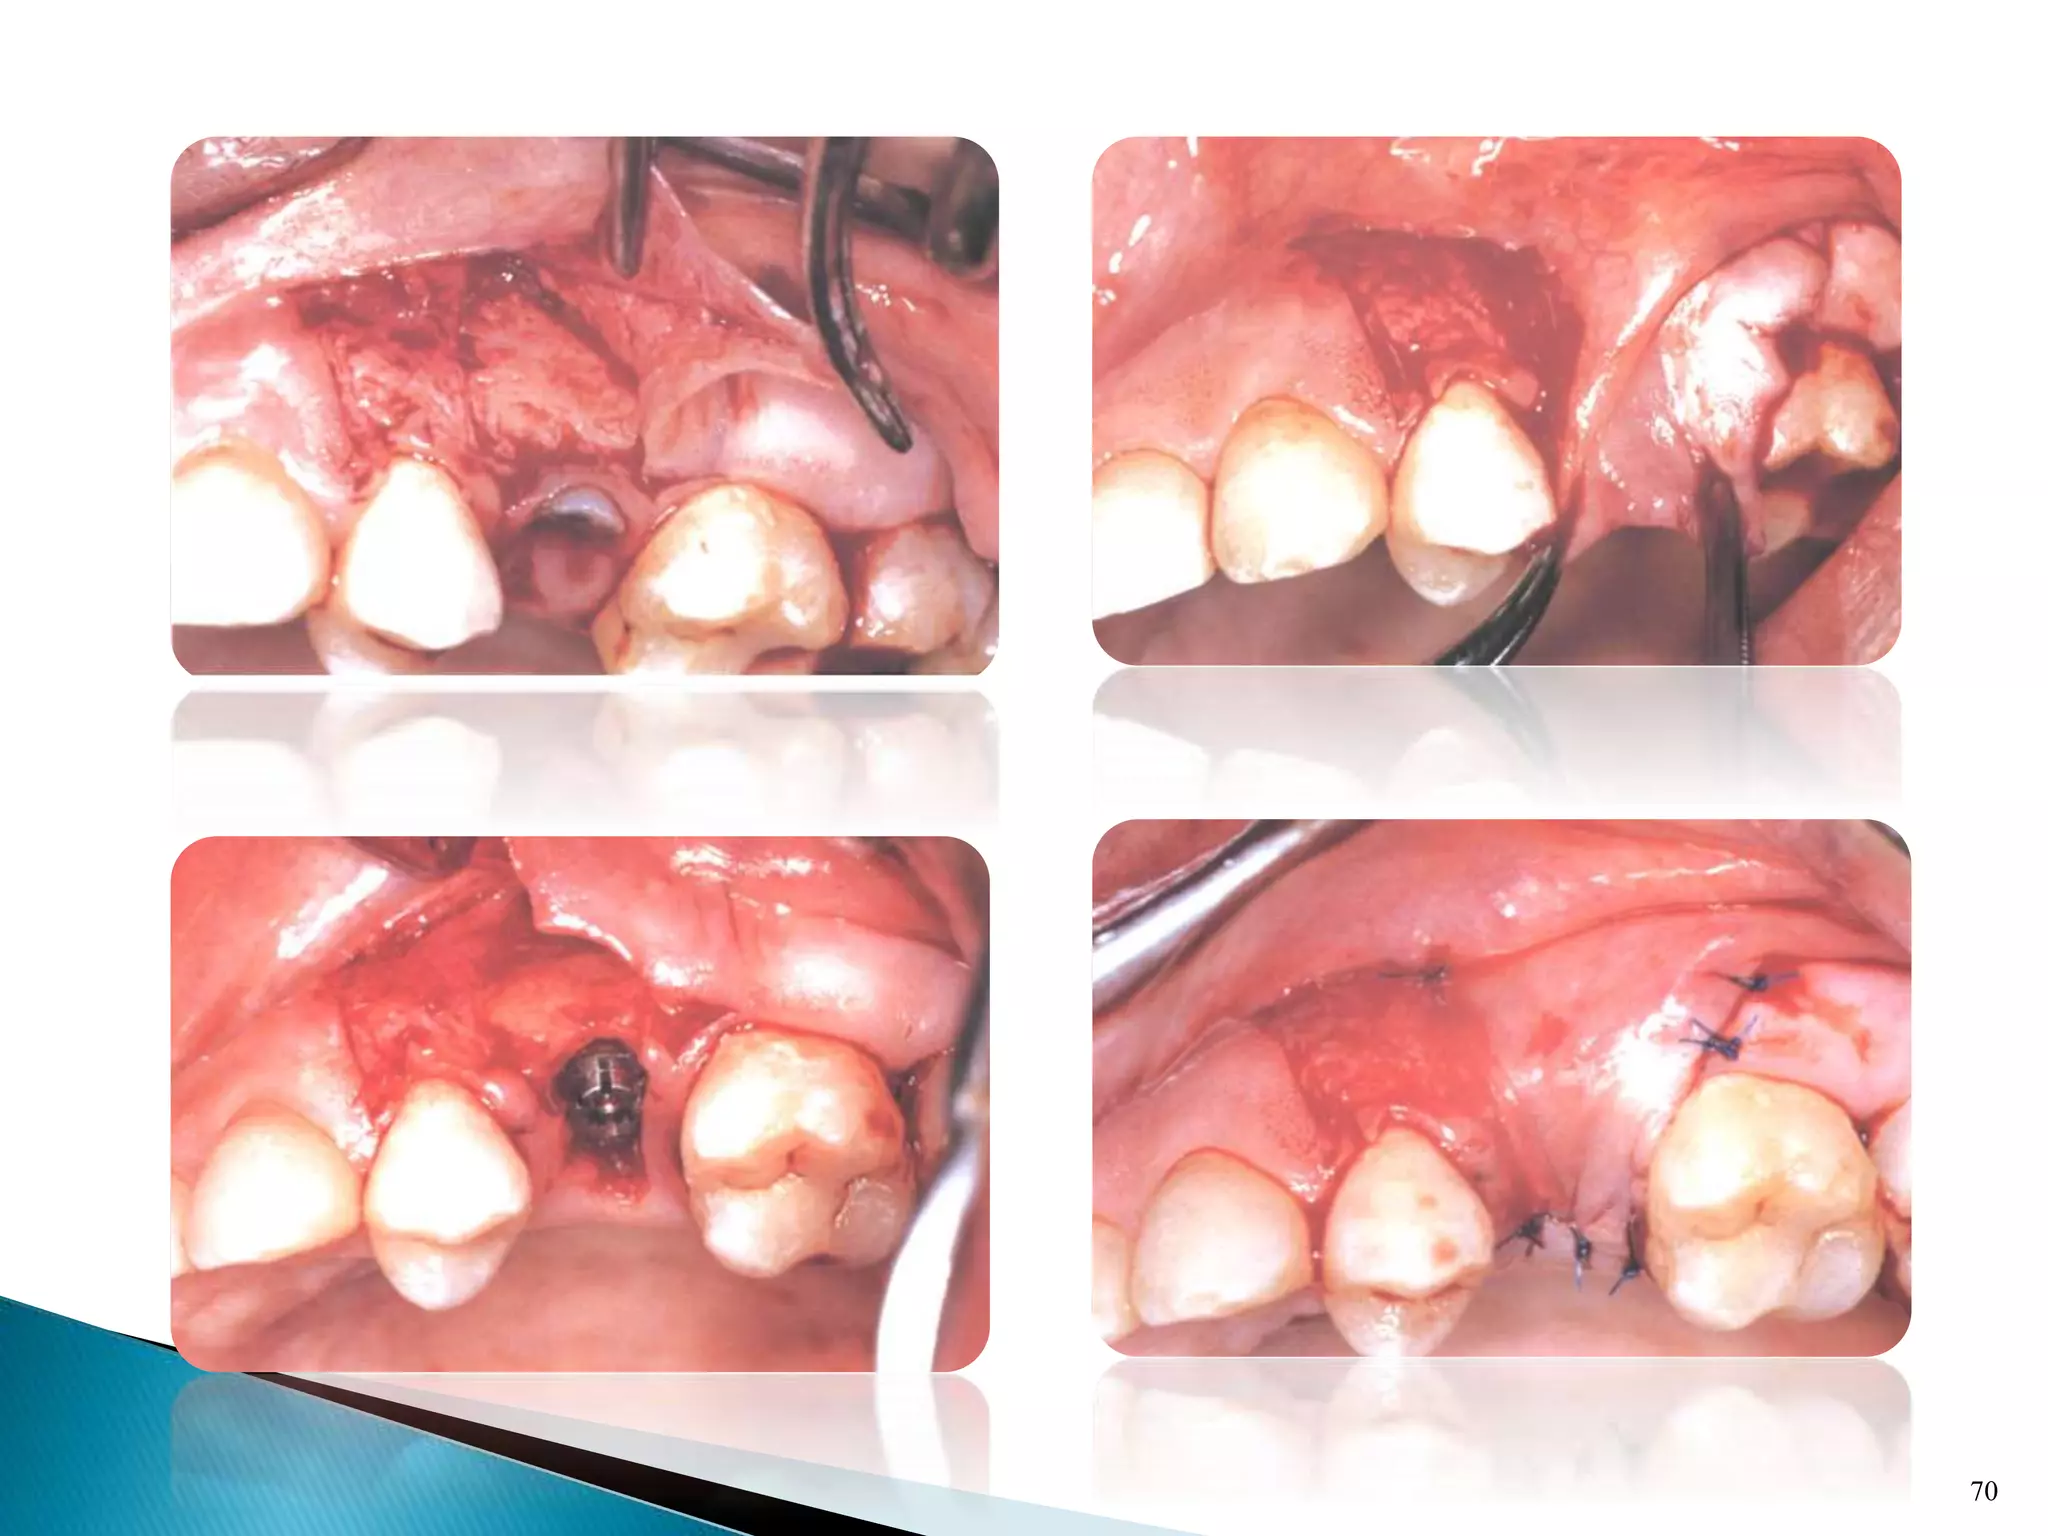

 Becker and Becker 1990 developed the buccal rotated flap

technique

 The technique can achieve a complete tension-free closure

without creating any mucoginigival discrepancies.

 Becker and Becker originally recommended a split thickness

flap from the tooth adjacent to the donor tooth to cover the

exposed bone on the donor tooth itself.

68

69

70